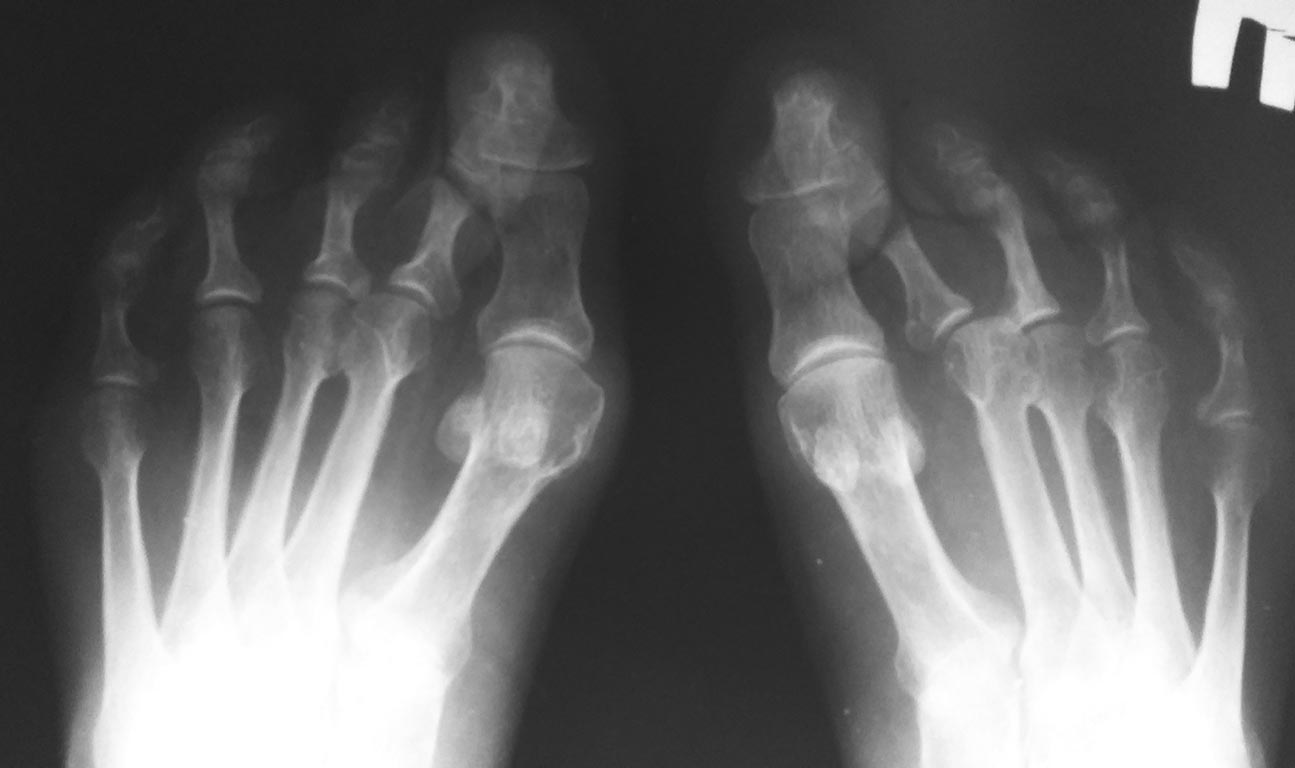

[Ortho] Проблема обеих стоп

Снимки